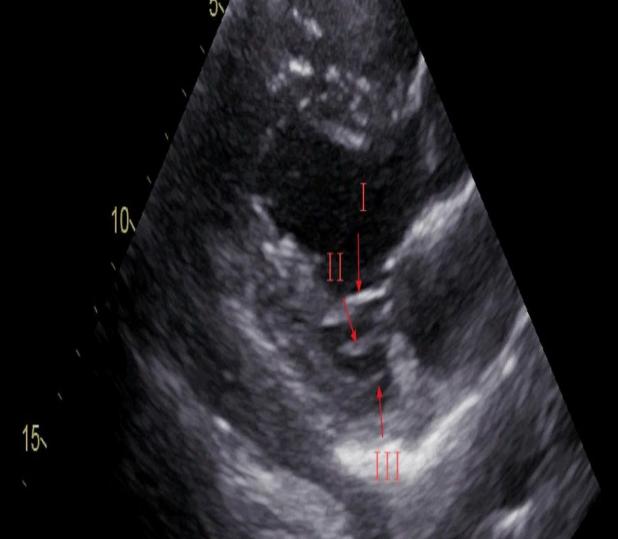

I级腱索:起自乳头肌,远端附着于瓣叶边缘,主要防止瓣叶边缘外翻。

II级腱索:起自乳头肌,附着于瓣叶中部,加强对瓣叶的牵拉作用。

III级腱索:发自左室壁,附着于瓣叶基底部,固定瓣膜位置的作用,只位于后叶。

对应到超声图像就是↓